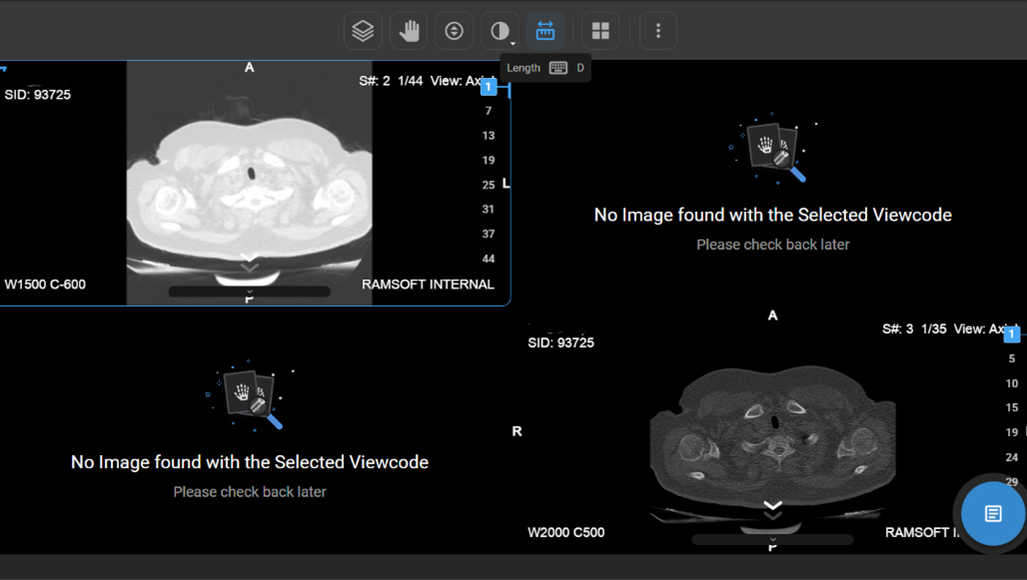

How Do I Measure Length?

• Usage: Measure distance between two points.

• Hotkey: Press D.

• Clinical Utility: Helps measure anatomical structures or lesion sizes.

• Locate the Length tool on the wheel and click on it to calculate the distance between two points on the image, useful for measuring anatomical structures.

vai